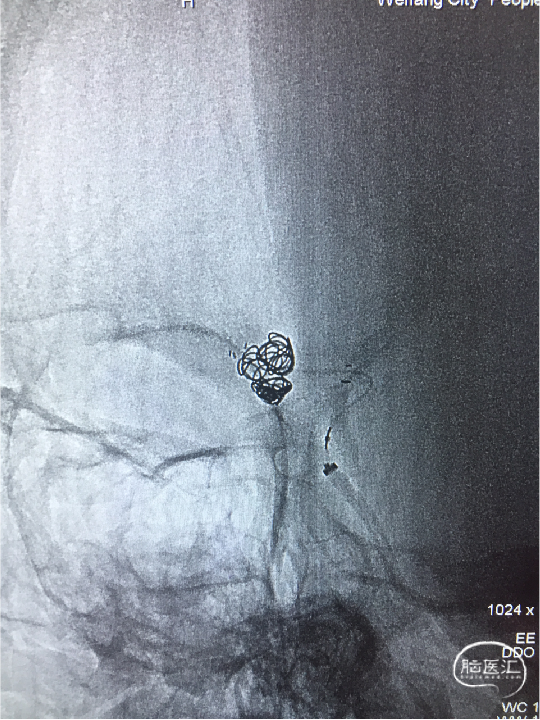

微导管到位

SL-10(直头)置于RACA A2,Atlas支架(直径3.0mm,较血管直径2.0mm大一号)到位,头端在RACA A2(左图);SL-10(头端S型)置于AcoAn左侧分叶(右图)。

支架释放

Atlas支架原位释放,头端打开良好,中部因较血管管腔大,可实现穹隆效果,以保护LACA A2流入道,尾端即将完全释放(左图);Atlas支架继续完全释放,尾端打开良好(右图)。